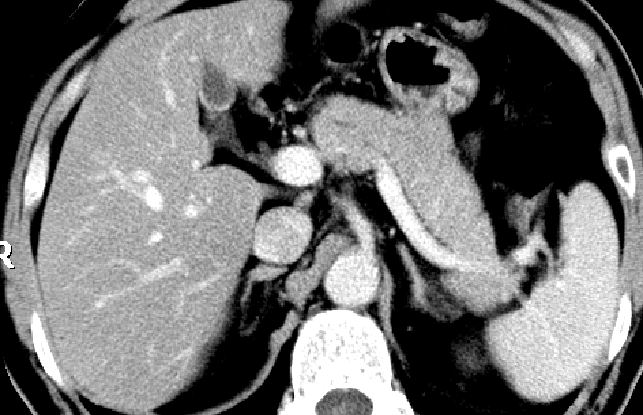

A:38岁,女患,急性间质水肿性胰腺炎,白箭头所示左肾周前间隙急性胰周液体积聚。胰腺完全强化,增大,但由于水肿导致强化不均匀。急性胰周液体积聚呈液体密度,无囊壁包裹。B:几周后,随访CT发现急性胰周液体积聚完全吸收,残留极少胰周脂肪毛糙影。

(2)CT对胰腺炎的严重程度有较大价值

CT-胰腺实质密度增高或降低,体积增大,胰周浸润。

增强CT-清楚显示胰腺坏死区域、范围